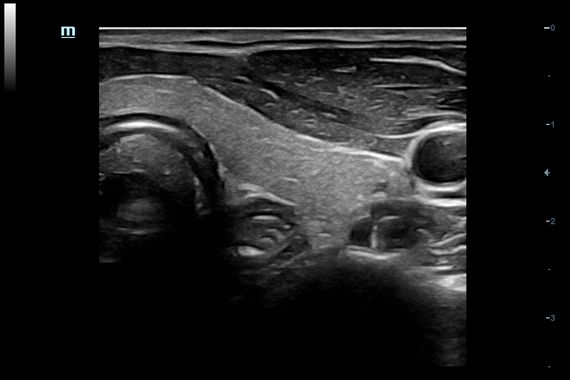

• Gynecology package - предустановленные параметры, аннотации, маркеры, программы измерений для гинекологии

• Внутриполостной датчик Mindray V11-3

• Ректально-вагинальный датчик Mindray V11-3B

• 3D/4D ректально-вагинальный датчик Mindray DE10-3E